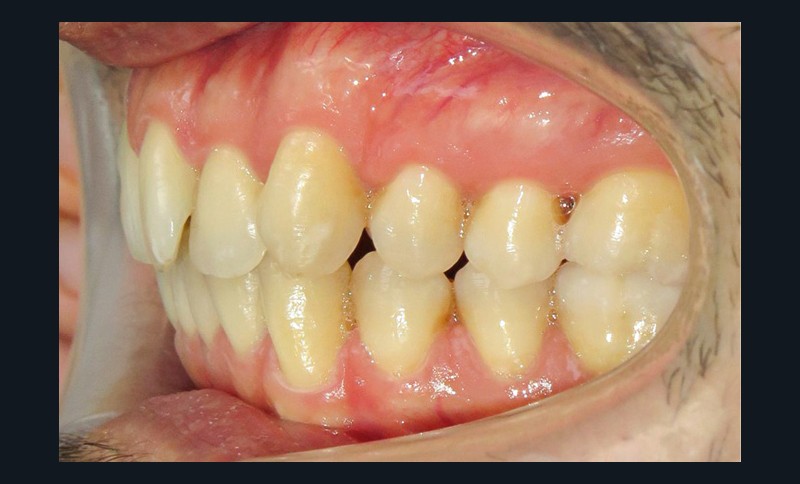

Diagnostic (fig. 1a-i)

Le patient consulte initialement pour des défauts d’alignement. L’examen clinique confirme l’existence d’un encombrement antérieur bimaxillaire, mais révèle aussi la présence d’une Classe II dentaire sévère, d’une exoclusion de la 27 et de troubles parodontaux (peu ou absence de papilles inter-dentaires). Sur le plan squelettique, le patient est relativement équilibré avec un profil harmonieux.